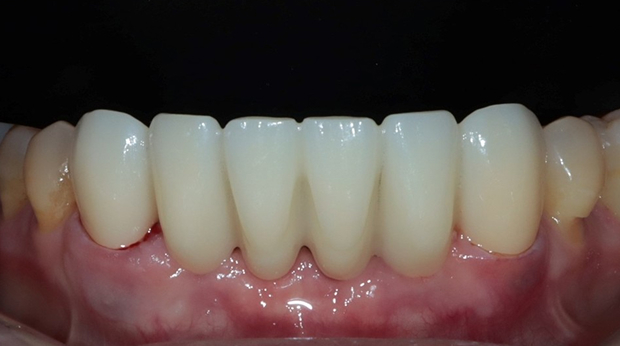

라미네이트